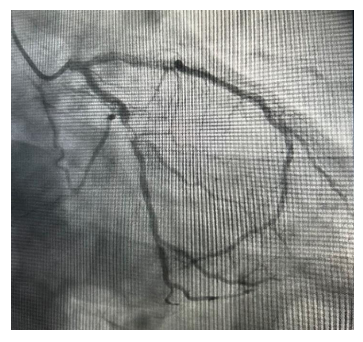

É encaminhado para a sala de hemodinâmica, onde se encontra a imagem a seguir.

O diagnóstico do paciente e a artéria acometida são, respectivamente: